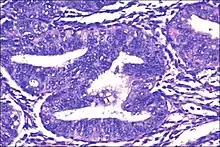

- Atypical endometrial hyperplasia (simple or complex) - Simple or complex architectural changes, with worrisome (atypical) changes in gland cells, including cell stratification, tufting, loss of nuclear polarity, enlarged nuclei, and an increase in mitotic activity. These changes are similar to those seen in true cancer cells, but atypical hyperplasia does not show invasion into the connective tissues, the defining characteristic of cancer. The previously mentioned study found that 22% of patients with atypical hyperplasia eventually developed cancer.[6]